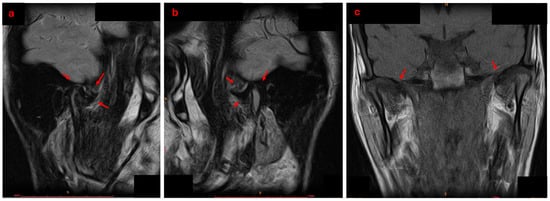

An Innovative Approach to Managing Temporomandibular Disorders Through the Combined Use of Two Oral Devices: A Case Report

by Antonio Spagnuolo, Roberta Iacono, Gian Mauro Liberatore and Carlo Di Paolo

Appl. Sci. 2026, 16(1), 273; https://doi.org/10.3390/app16010273 - 26 Dec 2025

Temporomandibular disorders (TMD) are increasingly prevalent in the adult population. Given the multifactorial and often chronic nature of TMD, the ideal therapeutic approach must be multimodal and personalized, with a preference for conservative treatments. However, standardized protocols combining occlusal devices and biobehavioral therapy for internal derangement (ID) are still lacking. Case Presentation: A 20-year-old male patient presented with bilateral anteromedial reducible disc displacement, with intermittent locking on the right. He reported joint noises, difficulty chewing, and occasional painful mouth opening. A comprehensive diagnostic workup, including clinical, functional, and radiographic evaluations, was performed. The patient underwent a biobehavioral gnathological therapy involving two oral devices: RA.DI.CA. and By-Te ® Reali. The protocol included personalized exercises, patient education, and behavioural counselling. Results. The patient achieved full remission of pain, disappearance of joint noises, and restoration of mandibular function, without dental movement. Pre- and post-treatment MRI and condylography confirmed improved condyle-disc relationships, increased intra-articular space, and better symmetry of movements, particularly on the right. Conclusion. The combined use of RA.DI.CA. and by-Te ® Reali devices, supported by a personalized functional programme, appears effective in managing TMD with ID. Further studies on larger populations are needed to confirm the efficacy and safety of this protocol. Full article